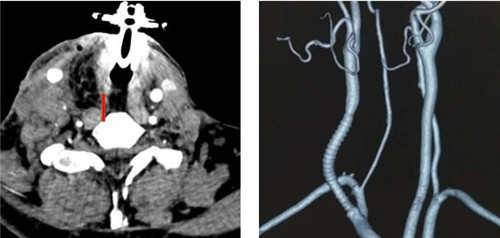

1:术前被肿瘤侵犯的动脉

术前,陈飞教授团队联合麻醉科陈泓羊主治医师对患者病情进行了充分评估,就术中颈总动脉处理、脑部血供维持、气道重建策略、循环维持等关键点展开了多次讨论,制定了严密的手术方案。630日,手术成功切除了复发的甲状腺癌、受肿瘤侵犯包裹长达8cm的颈总动脉、部分颈内静脉、锁骨下静脉、椎静脉以及被侵犯的颈段气管右侧壁。肿瘤完整切除后,在颈动脉转流管有效保证术侧脑血管灌注的情况下,进行了人工血管置换重建颈总动脉,显微缝合修补/重建受累静脉,恢复了颅内外正常血供。最后,应用右侧胸肩峰动脉穿支皮瓣同期修复了颈段气管缺损,手术历时4小时。手术后患者安全返回耳鼻咽喉·头颈外科病房,接受了近1周治疗和悉心护理,现已顺利康复出院。